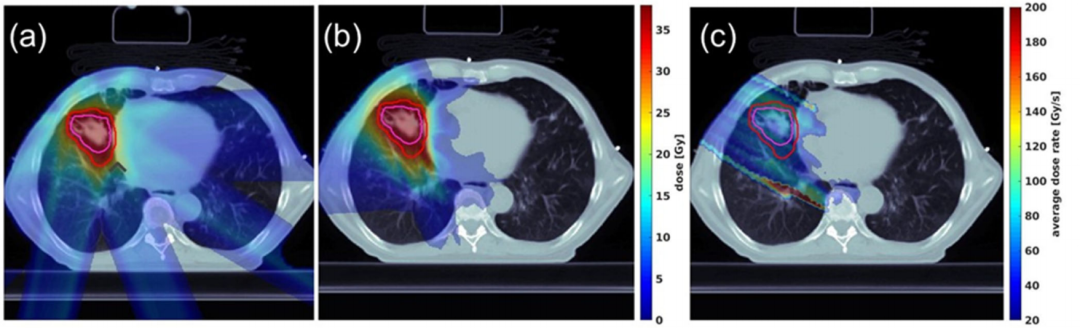

圖3.透射式和布拉格峰式肺癌的FLASH質子計劃二維劑量分布比較。(a)典型的FLASH質子PBS透射式計劃;(b)典型的單能質子PBS布拉格峰式FLASH肺癌計劃,計劃中的劑量處方為每分次18 Gy;(c)一個單能質子布拉格峰式計劃射野的平均劑量率分布,結果顯示大于40 Gy/s的平均劑量率分布能夠在大部分正常組織中實現